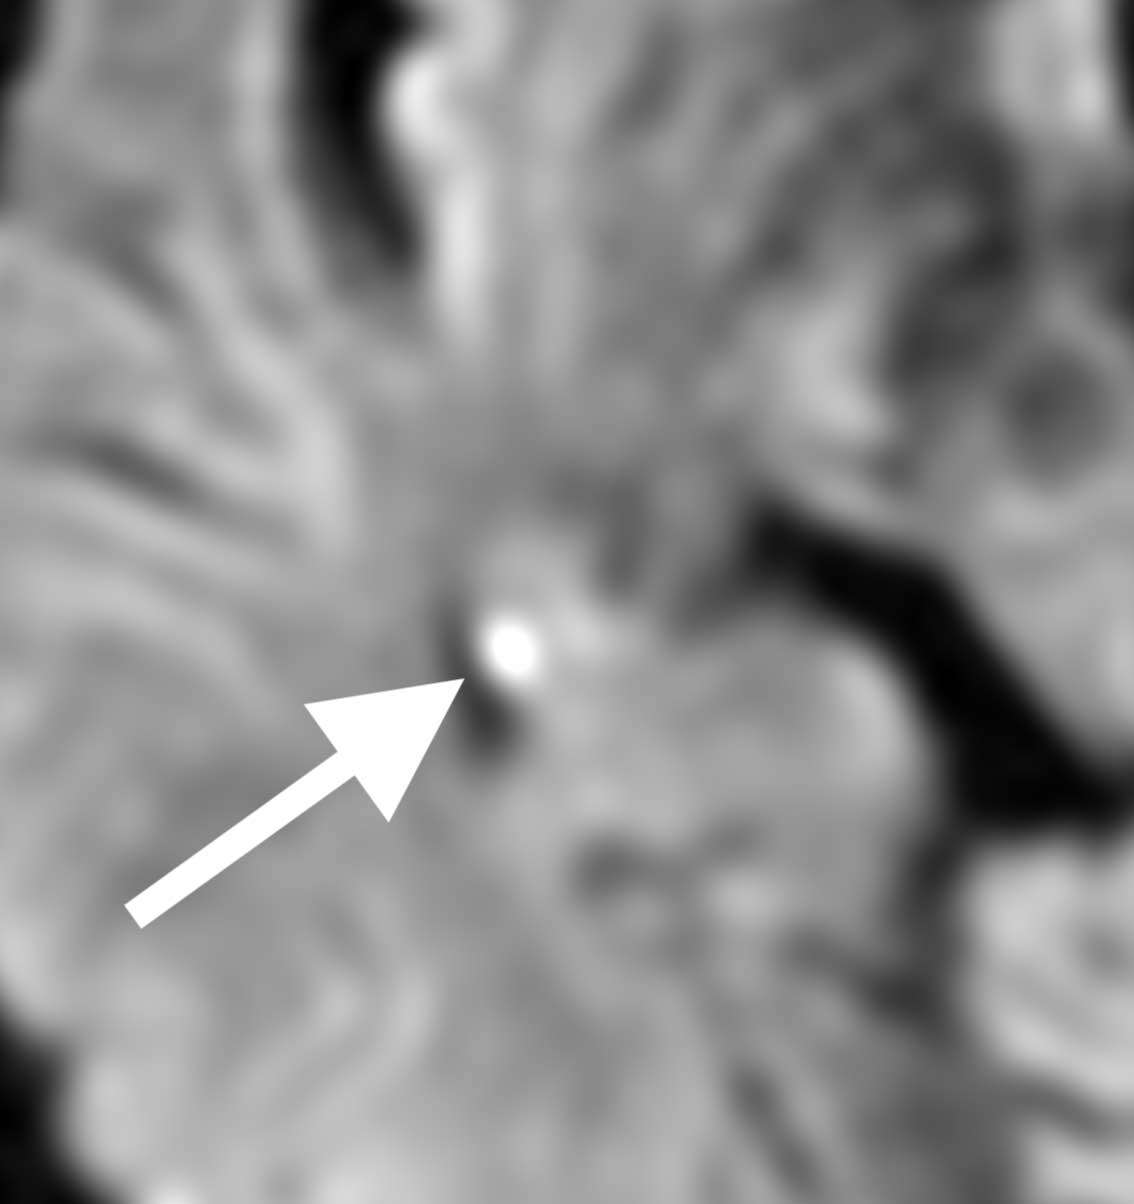

MRI検査(拡散強調画像)を確認すると、

右の海馬に白く光っている部分があり、やはり微小な脳梗塞と診断しました。